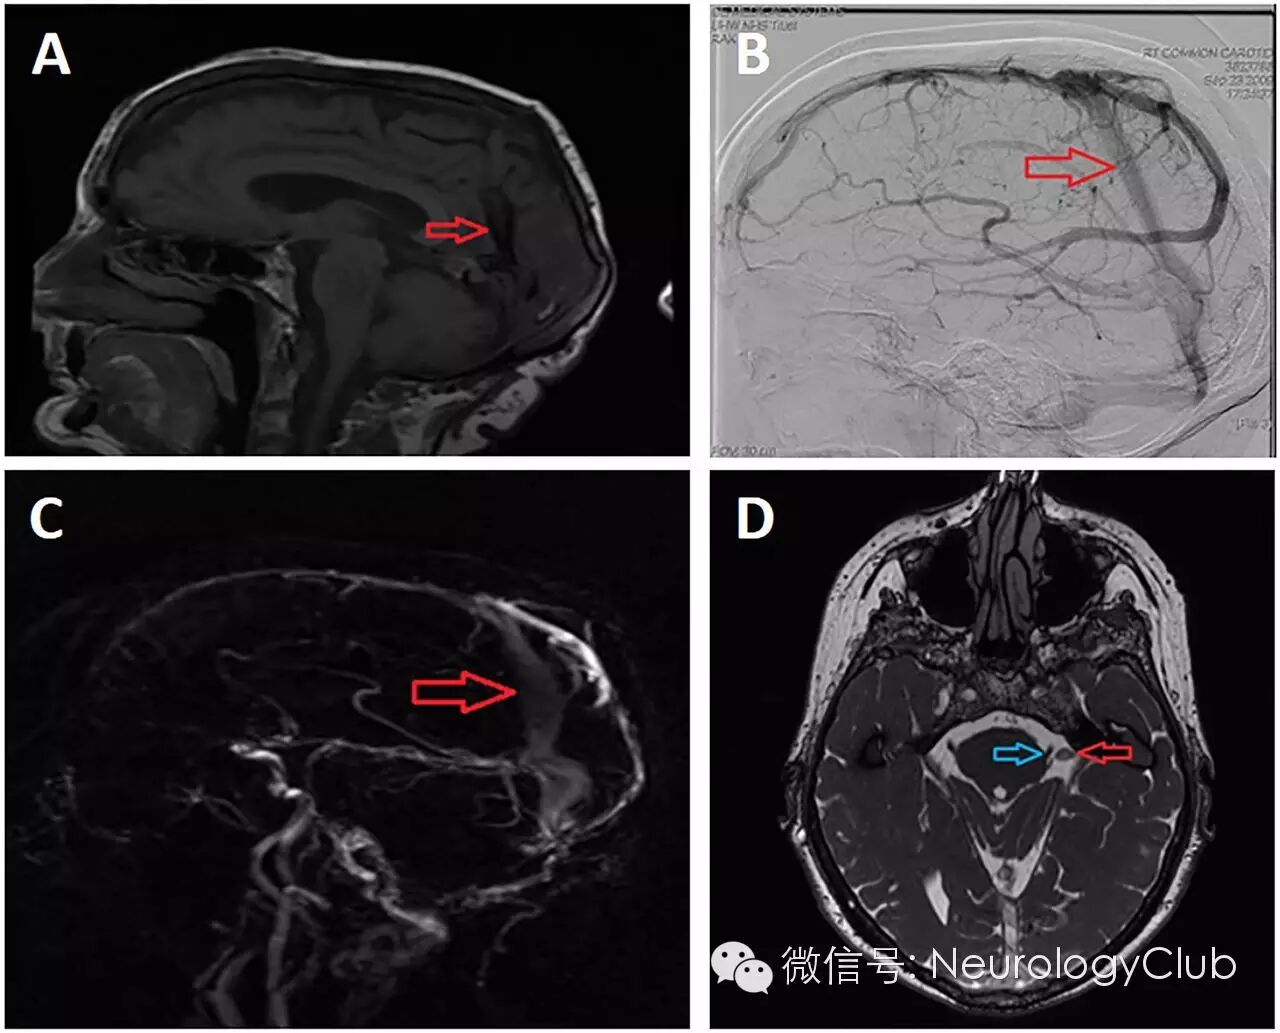

(A-C:矢状位MR血管造影可见从矢状窦往下的静脉异常[红箭];D:T2WI证实静脉异常邻近三叉神经根)